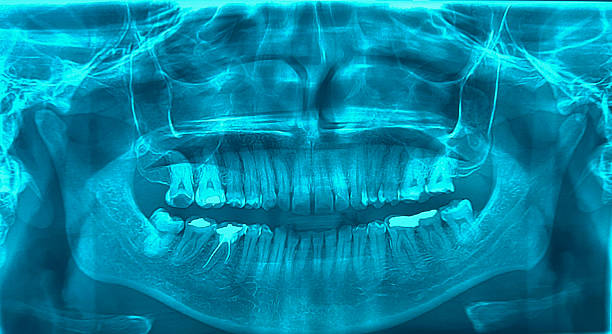

By Technology – X-Ray Systems, Dental Cone Beam Computed Tomography, Magnetic Resonance Imaging, and Others By Method – Intraoral Imaging and Extraoral Imaging), By End User (Dental Clinics, Dental Laboratories, Dental Research and Academic Institutes and Others